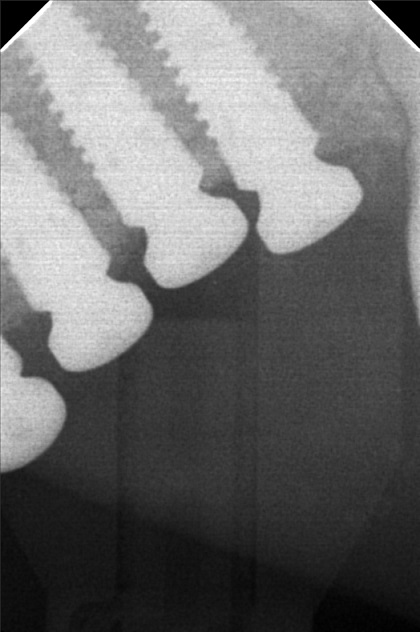

Edit Record Check our patient data records. Add patient information Patient Info Profile picture Last Name First Name Middle Name Birthdate Age Street Barangay City Country Zip Code Contact number Email Procedure 07/26/21- implant placement- 16-8.5mm 15-8.5mm/ 47/46/36/37 with prf/ cgf/ bone fillers 11/13/21 - 15 healing abutment installed- 3mm (6mm) 46/45 healing abutment installed- 6mm req for 3mm 12/17/21 - installation of abutments/ impression 12/22/21- PMMA 46/47/36/37 (12/29) final impression 2/3/22 - 4 implants 4.3x10mm lateral sinus lift LEFT 05/07/22- OP with ozone PA xray 05/13/22 recementation 22 veneers 05/31/22- Redo 23 Veneers PFZ- Temporary ***for healing abutment implants 08/12/22- installation of healing abutments 9/6/22- scan body/ intra oral scanned ***request for alginate impression *** shade A3 cervical A2 body 10/07/22- installed 4 units 24/25- with pink porcelain crown 26/27 ameloplasty mesial of 28 abutment sealed with TF Zirconia crown- screw retained 12/17/22- OP 05/13/23- xray/ozone 09/23/23- OP/AIRPOLISHER XRAY 10/13/23 -RCT #41 - flexion root opening - dressing formocresol 10-27-23- RCT #41 18.5 mm Champenol Flexion root 11-03-23- Obturation #41 MTA Fillapex, Master wire = fine 11/10/23 # 43 - veneer; emax # 42 - veneer; emax # 41 - crown; PF Z # 31 - veneer; emax # 32 - veneer; emax shade A3/ B2 11/17/23- Installation of Veneers- 43,42,31,32 (emax) Crown Zirconia- 41 Cement: choice 2 Prosapac Vacummed sheet retainer 05/25/24 OP w/ air polisher 03/29/25 OP w/ air polisher LC #42 (I) cementation repair veneer 06/13/25 Upper #23-PFZ Lower # 32,33- Zirconia bal.70k 06/18/25 installed PFZ crown #23 zirconia crown #33,#32 bal,. paid 08/08/25 Dx:peri implantitis #44/15 moldable bone-HUBT .m30 w/PRF #44 implant moldable bone HUBT .m30 w/ PRF #15 scaling and planning disinfect w/ citric acid irrigate w/ citric acid Rx: Celecoxib 400mg Tranexamic 500mg Co amoxiclav 625mg, Orahex Prednisone 10mg for 10 days 02/24/26 LC on iplant #25-Occ #23- Recement veneer 02/25/26 Repair 04/01/26 #13 DCV File 01cb0af9-a7ec-487f-a76f-2b7aa0463be3.jpeg File 2 9941df4f-eadd-49c9-a9ad-b0f3e6f2052a.jpeg File 3 2d4f20db-c762-4f0e-9fe3-4a3ecc7b62c0.jpeg File 4 a55f6852-691c-4c51-ad5c-f6f58a1f269c.jpeg File 5 a965f478-086f-4edc-bdde-4c4f9bcd41ff.jpeg File 6 d31d3680-98bc-43a6-bcb1-c3d0d4b8c1c5.jpeg File 7 roleenxray.jpg File 8 roleen_del_prado.jpg File 9 rollen_del_prado_02.jpg File 10 rpleen_del_prado_04.jpg File 11 1000005163.jpg File 12 File 13 File 14 File 15 File 16 File 17 File 18 File 19 File 20 Retain Record Retain Record Yes No Save Your Changes